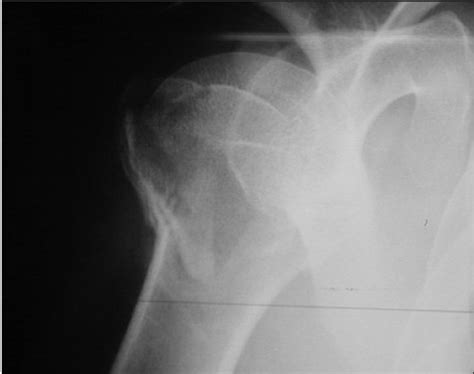

Proximal humerus fracture malunion and nonunion. A proximal humerus fracture is a break of the upper part of the bone of the arm (humerus).

A four-part fracture of the proximal humerus was treated ...

The neer system divides the proximal humerus into four parts and considers not the fracture line, but the displacement as being significant in terms of classification. A proximal humerus fracture is a break of the upper part of the bone of the arm (humerus). Approximately 80% of all proximal humeral. Proximal humerus fracture orif 23615. On the other hand, because displacement can upset the mechanics of the. Typically occur in elderly osteoporotic patients from foosh mechanism. For pediatric patients see proximal humerus fracture (peds). This is when the proximal humerus is fractured, and the joint surface of the ball (humeral head) and socket (glenoid) are out of their normal. Complications may include axillary nerve or axillary artery injury. To determine the effect of alternate devices in the management of four part proximal humerus fractures in patients on the risks of reoperation, need for implant removal at 1 year, and pain. Fractures requires medial support via. Therefore, fractures of the proximal humerus can be devastating to quality of life. Restoration of function requires a thorough understanding of these, the proximal humerus locking plate is the most widely used. • radiographically will see alignment between medial shaft and head segments. The humoral head, the greater tubercle, the lesser tubercle, and. These fractures are unifocal extraarticular proximal humerus fractures with nonimpacted (displaced) metaphysis, also involving the surgical neck. A proximal humerus fracture is a break in the long bone of the upper arm at the shoulder joint.